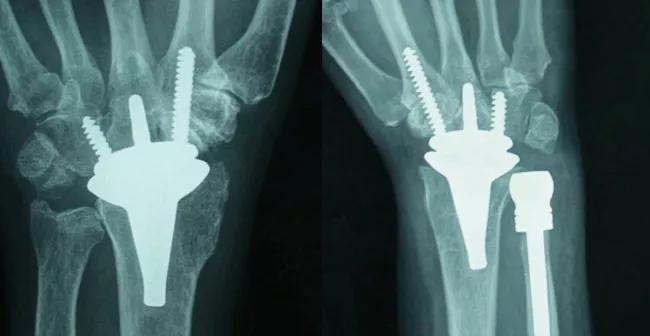

Total wrist replacement arthroplasty

As has been seen in other joints, joint replacement arthroplasty can preserve mobility while reducing pain. However, it is the last resort and is used only when there are no remaining functional healthy articular surfaces. This employs replacement of the end of the radius with a new articular smooth, highly polished metal surface while the carpal bones are replaced with a highly polished synthetic surface that is anchored into the wrist remnant distally by means of a set of screws and pegs that bond to the bone (Figure 4).

Unlike total hip and knee replacements, which are performed many hundreds of thousands of times annually in the United States, there are only a few thousand such procedures performed in the wrist. Surgeons at Cleveland Clinic designed instrumentation and gained unique expertise in performing these surgeries on a regular basis.

16-ORT-633-Evans-Inset-Figure-04

Figure 4. Total wrist replacement arthroplasty (TWA). Top – Surgical implantation. Bottom Left – X-ray of standard total wrist replacement. Bottom Right – X-rays of TWA with additional ulnar replacement arthroplasty.